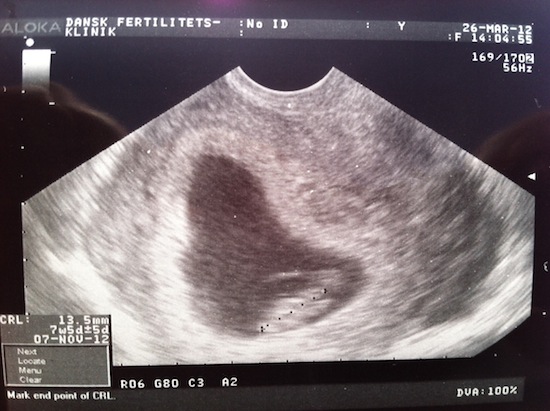

Vi har også været til to scanninger tidligere på grund af vores forhistorie. Det har vi været meget glade for, da det har givet lidt mere tryghed.

1. scanning 1. scanning - 26. marts, 13,5mm